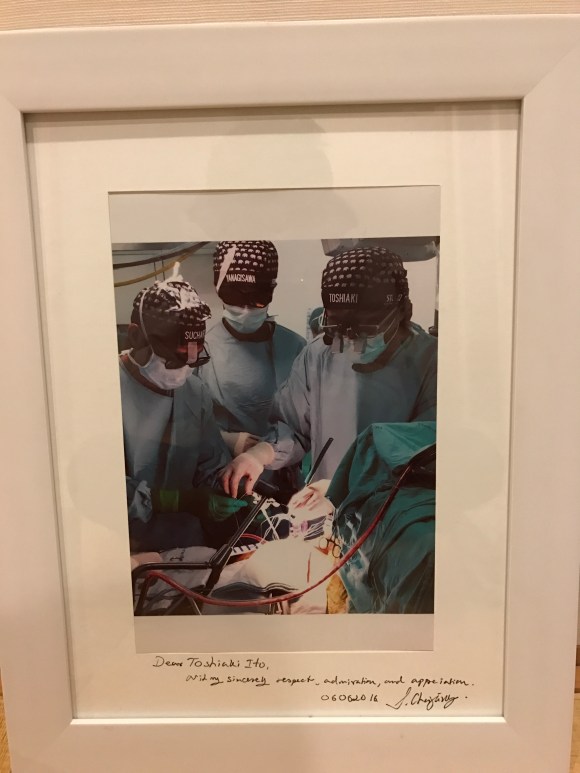

不要でfemoral vein1本脱血で右房が開けられます。脱血も今のところ全例(10例程ですが)良いので、このカニューレは使えると思います。 1月某日、3D完全内視鏡下僧帽弁形成、三尖弁形成、メイズのMICS手術見学コースを開催しました。今回は新しいデバイスを2個使用。Atricureのクライオシステムと、Biomedicusの2-stage脱血管です。共に海外ではずっと前からMICS手術の標準デバイスであった物がようやく使える様になり随分手技が簡略化出来、丁度4時間で手術が終わりました。その後ブリーフセミナーを行った後の写真が上です。今回は大御所のお姿が。

1月某日、3D完全内視鏡下僧帽弁形成、三尖弁形成、メイズのMICS手術見学コースを開催しました。今回は新しいデバイスを2個使用。Atricureのクライオシステムと、Biomedicusの2-stage脱血管です。共に海外ではずっと前からMICS手術の標準デバイスであった物がようやく使える様になり随分手技が簡略化出来、丁度4時間で手術が終わりました。その後ブリーフセミナーを行った後の写真が上です。今回は大御所のお姿が。